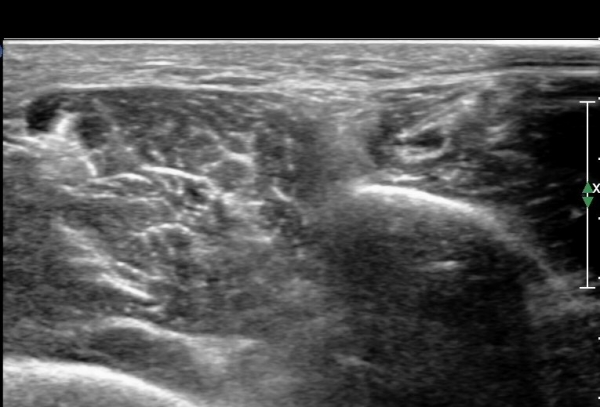

¾Æ·§´Ù¸® ¿ÜÃø Ⱦ´Ü¸é°Ë»ç¿¡¼ Àåºñ°ñ±Ù°ú ¹ß°¡¶ô½ÅÀü±Ù »çÀÌ¿¡¼ õºñ°ñ½Å°æÀÌ Á¤»óÀûÀ¸·Î °üÂûµÈ´Ù(»çÁø 1, , 2, 3, 4, 5).